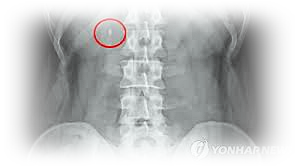

이러한 결석은 보통 신장에서 발생합니다.

신장, 요도, 방광, 요도 등에 있습니다